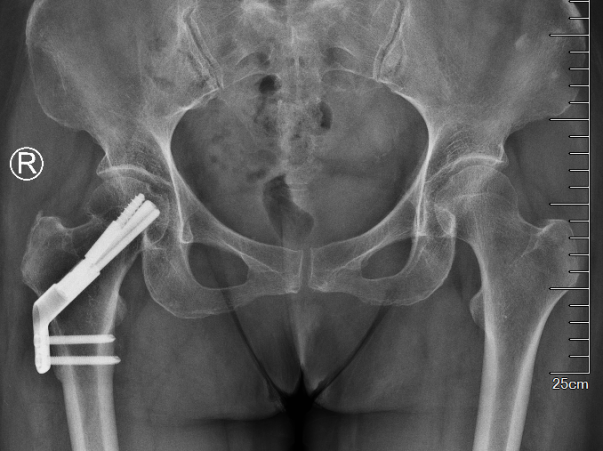

近日,我院骨科一区成功独立开展治疗股骨颈骨折的FNS(股骨颈动力交叉钉系统)微创手术,患者术后复查股骨颈已骨性愈合,...